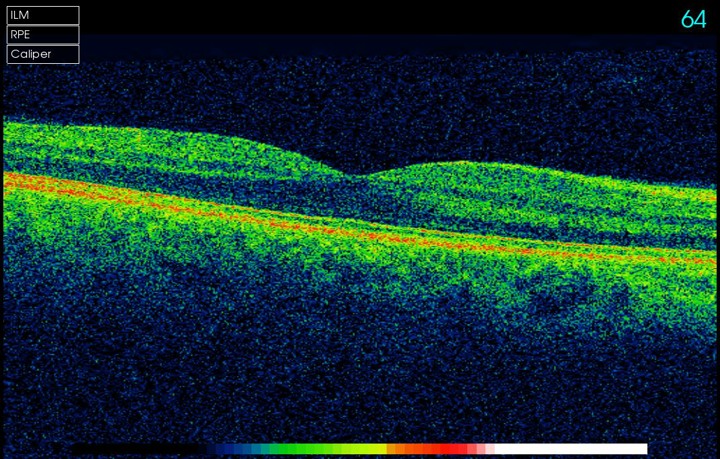

The instrument is incredibly good at measuring and monitoring Macular Degeneration.  It can measure the thickness of the optic nerves which are affected by Glaucoma (and compare to an age, gender and ethnically matched normal).

A 3D section of the layers ofthe retina and vitreous jellyA 3D section of the layers of the retina and vitreous jellyAge-related Macular Degeneration Dry FormAge-related Macular Degeneration Dry FormAge-related Macular Degeneration Wet FormAge-related Macular Degeneration Wet FormThe vitreous (jelly) pulling on the retinaThe vitreous (jelly) pulling on the retinaImage of Retina (back of the eye)Image of Retina (back of the eye)